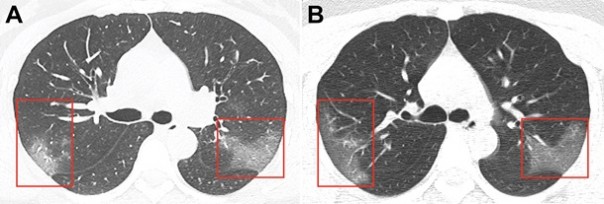

Снимки были получены в результате компьютерной томографии 33-летней женщины, госпитализированной в китайском городе Ланьчжоу с температурой 39 градусов.

Снимки были сделаны с разницей в три дня. На первом из них в низу легких уже заметны зоны поражения инфекцией - они похожи на большие светлые области. На снимке, сделанном спустя три дня уже заметно, что зона поражения расширяется.